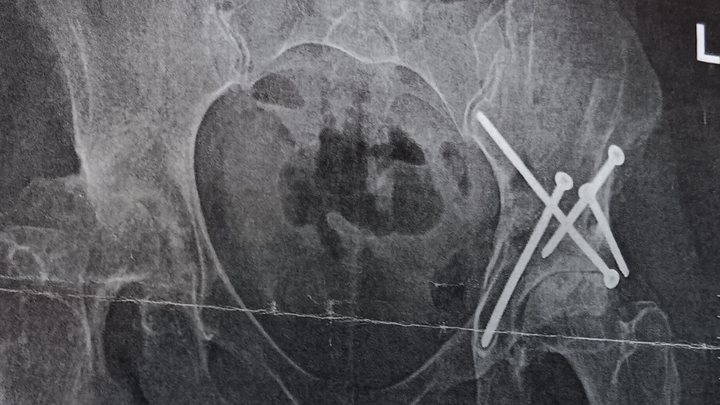

I was born with congenital hip dysplasia and underwent 9–10 surgeries before the age of 3. I thought I had left those struggles in the past — but recently, the pain returned, stronger than ever. At work, I felt a deep, grinding, breath-stealing pain in my hips that stopped me in my tracks. Soon, even simple things — putting on socks, cleaning my tiny home, driving, or walking my dog — became too much to bear.

Now I’m facing a new challenge: severe osteoarthritis in both hips, requiring surgery. The pain is constant. Work has become nearly impossible — and with it, so has keeping up with bills during my recovery.